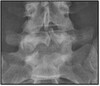

What are the radiographic signs of Paget's disease

Bones affected have a mottled, cotton-wool appearance (from irregular formation)

What pathology is seen here?

Paget's disease

284

Paget's disease (note cotton ball appearance)